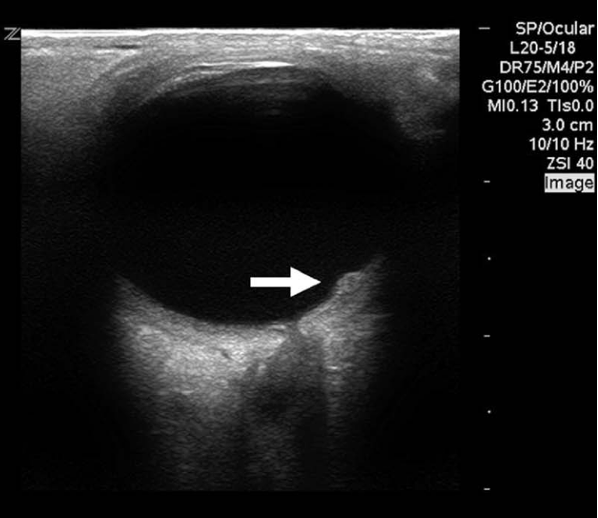

Decreased global function:

LVfx is considered reduced if the LV walls fail to contract effectively toward the center of the cavity during systole. Wall motion will appear sluggish or diminished, and the overall inward movement and thickening will be reduced.

Size and Shape:

Decreased LV systolic function is often accompanied by dilation, such as in dilated cardiomyopathy. The LV loses its normal ellipsoid or bullet shape, appearing globular or rounded, and is much larger than the right ventricle.

Figure 2b. Severely decreased function, globally seen in the A4C view